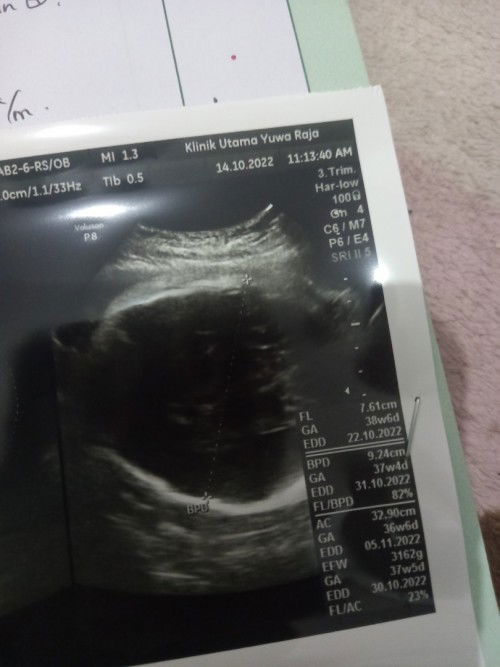

Boleh sharing disini bu ibu yg lahirnya lewat HPL saya udah 38 week 6 hari BBJ udah 3,1 tapi belum kerasa mules pas udah cek panggul udah mulai turun kata spog nya sabar aja banyak berhubungan aja sama suaminya , biasanya lewat hpl brp lama yaa ? Saya takut kalo lwt hpl ketubannya keruh kasian dedenya ##bantusharing #ingintahu #firstmom #firstbaby